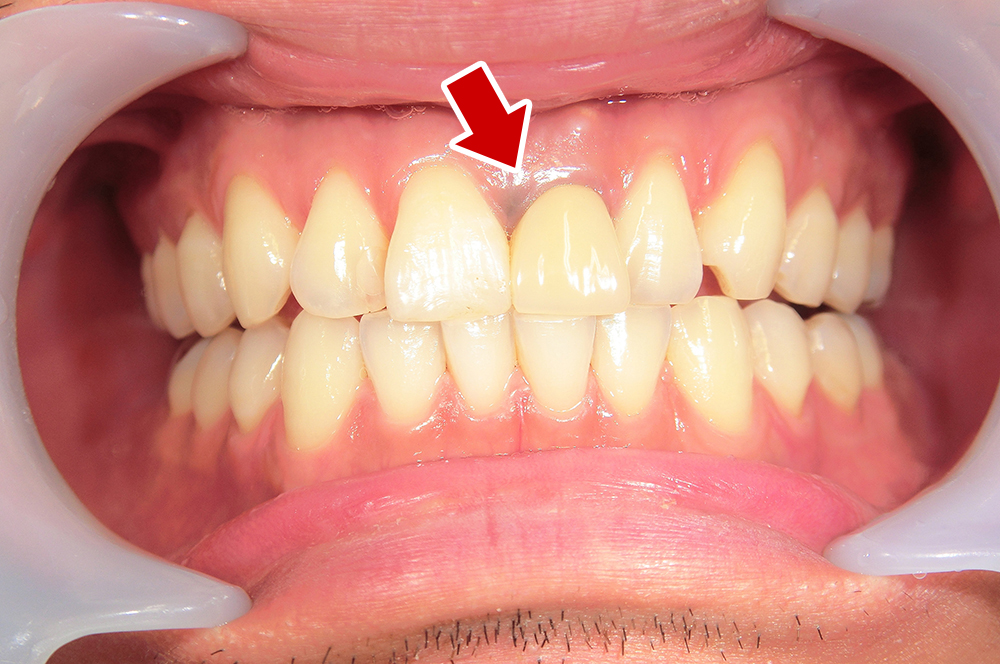

29歳 男性 歯科医療関係者紹介。また、お姉さんが歯科医療関係者。

- 左上1番目の歯が長期にわたり痛く、噛めない。

1本インプラント埋入+再生療法。抜歯即時埋入、即時荷重法⇒抜歯を行い、

同時にインプラント埋入(即時埋入)、そして同時にインプラントへ仮歯を装着(即時荷重)

歯が無い期間なく、社会生活に支障が出ない

- その他

- 学術雑誌、海外公演(アメリカ、ヨーロッパ)に多く紹介されたケース